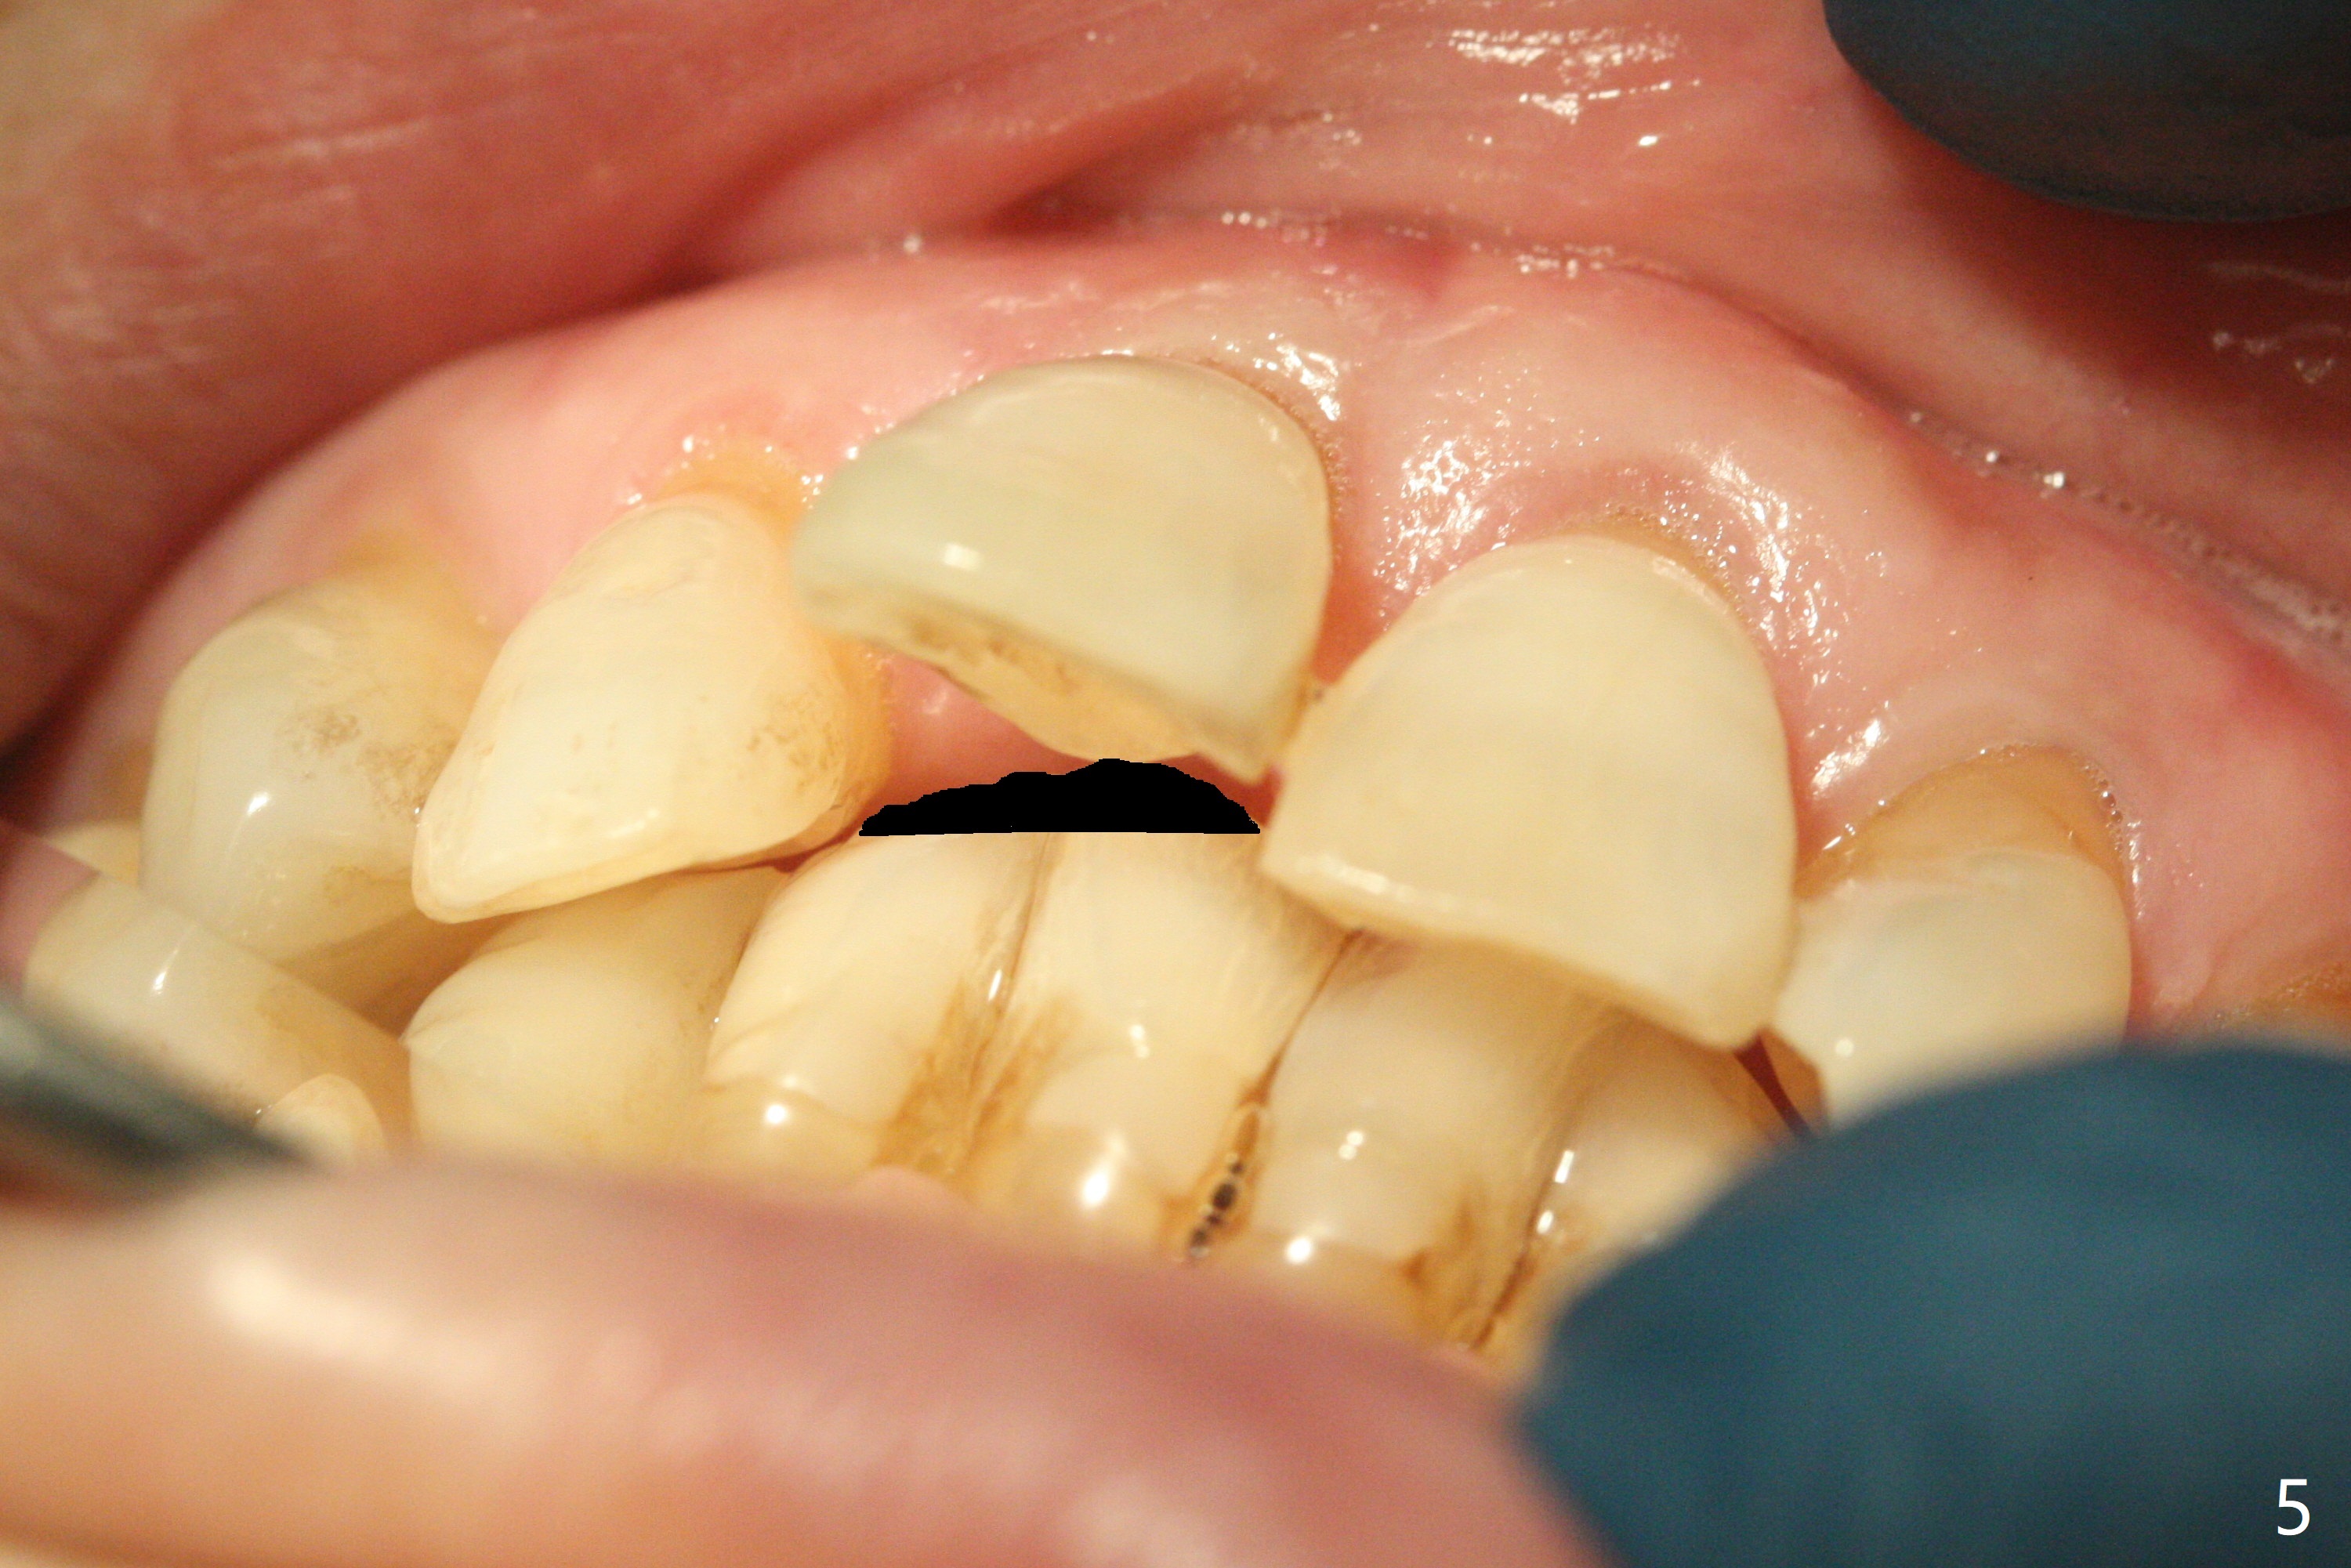

59岁女今天就诊,“上门牙快掉下来”,检查表明右上1延长(图一:长箭头),牙龈退缩(短箭头),红肿(*),颊侧骨板触诊不觉得塌陷(图二)。咬合时,患牙前移(图三),伸长的下切牙(图三,九:1,2)造成咬合创伤。因此拔牙前,将降低下门牙切缘(图四,五(黑色)),为临时牙冠创造足够修复空间。CT冠状切面显示颊侧(图六:B)骨板缺失,可以植入两段式植体(3.5x11.5 毫米),但是最细基台(4毫米直径,图七(粉红色和蓝色))显得太粗,不利于腭侧修复空间形成,而2.5x14(4)毫米一段式植体不仅创造更多颊侧植骨空间(图八(红箭头)),而且由于固有基台直径小(白箭头),容易形成腭侧修复空间。一旦前牙植体永久性修复完成,督促病人做三个第二磨牙植牙修复(图九:7),减少对前牙植牙创伤。临时牙冠不仅解决美观问题,而且固定骨粉,保持颊侧骨板隆起,维持牙龈缘和乳头。在大多数情况下,使用现成树脂牙冠(crown form)制作临时修复物,这个病例牙齿完整,截除的牙冠可以用来做临时牙冠。